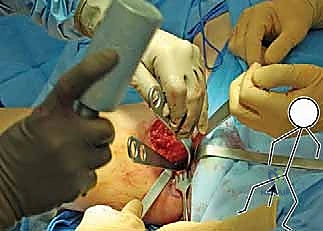

تعتبر هذه الجراحة تحفة فنية هندسية في عالم العظام. يطلق عليها "الثلاثية" لأن الجراح يقوم بقطع ثلاثة عظام رئيسية تشكل الحوض لتحرير التجويف الحقي بالكامل. إليك الخطوات التفصيلية كما يجريها الأستاذ الدكتور محمد هطيف:

تُجرى العملية تحت التخدير العام. يُوضع المريض على طاولة العمليات بوضعية تسمح بالوصول الكامل إلى منطقة الحوض، مع استخدام المراقبة العصبية المستمرة لضمان سلامة الأعصاب الكبرى في الساق (مثل العصب الوركي والعصب الفخذي).

2. الشقوق الجراحية (Incisions)

يُجري الدكتور هطيف شقوقاً استراتيجية مصممة لتقليل الضرر العضلي وترك ندبات تجميلية صغيرة قدر الإمكان. يتم الوصول إلى العظام الثلاثة بعناية فائقة وتجنيب الأوعية الدموية الحساسة.

3. مرحلة القطع العظمي (The Three Osteotomies)

هنا تكمن عبقرية الإجراء. يتم استخدام مناشير جراحية دقيقة لعمل قطوع في:

* عظم الإسك (Ischium): العظم السفلي الخلفي للحوض.

* عظم العانة (Pubis): العظم الأمامي للحوض.

* عظم الحرقفة (Ilium): العظم العلوي العريض للحوض.

بمجرد اكتمال هذه القطوع الثلاثة، يصبح التجويف الحقي (الكوب) منفصلاً تماماً عن بقية الحوض، مع بقاء إمداداته الدموية سليمة.